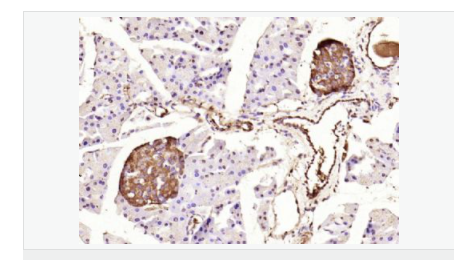

交叉反應(yīng):Human,Mouse,Rat(predicted:Dog,Pig,Cow,Rabbit,Sheep,GuineaPig) 推薦應(yīng)用:IHC-P,IHC-F,ICC,IF,Flow-Cyt,ELISA

產(chǎn)品應(yīng)用ELISA=1:5000-10000 IHC-P=1:100-500 IHC-F=1:100-500 Flow-Cyt=1ug/Test ICC=1:100-500 IF=1:100-500 (石蠟切片需做抗原修復(fù))